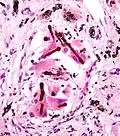

_by_core_needle_biopsy.jpg)